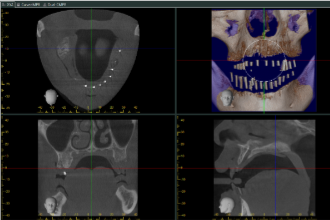

第二步|模型分析與電腦斷層掃描(CT)

在口腔結構穩定後,進入進階分析階段:

- 模型分析:確認咬合習慣、上下顎關係、贗復空間,避免日後假牙咬合不良

- CT掃描:檢查顎骨高度與寬度,模擬植體最佳位置,提升全口植牙準確性

- 融合數據:透過3D整合資訊,為後續假牙設計提供最精密依據

這一階段正是全口重建推薦療程與傳統假牙最大差異之一,我們讓「預測」成為「確定」。